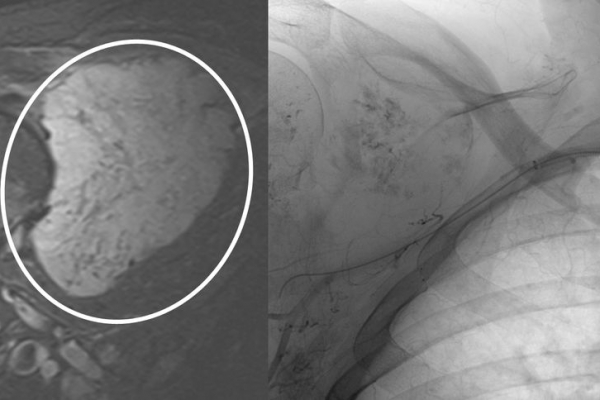

♦ Όγκους

Είτε προεγχειρητικά για την ελάττωση της αιμάτωσης του όγκου, είτε θεραπευτικά σε ορισμένες περιπτώσεις που δεν απαιτείται χειρουργείο ή υπάρχει αντενδειξη για χειρουργική αφαίρεση του όγκου.

Συνοπτικά υπό την καθοδήγηση του αγγειογράφου, αναγνωρίζεταιτο παθολογικό αγγείο-αγγεία και με ειδικούς καθετήρες και μικροκαθετήρες, διοχετεύονται εμβολικά υλικάόπως μικροσφαιρίδια ή coils, ώστε να αποφραχθεί ή να μειωθεί η παθολογική αγγείωση.